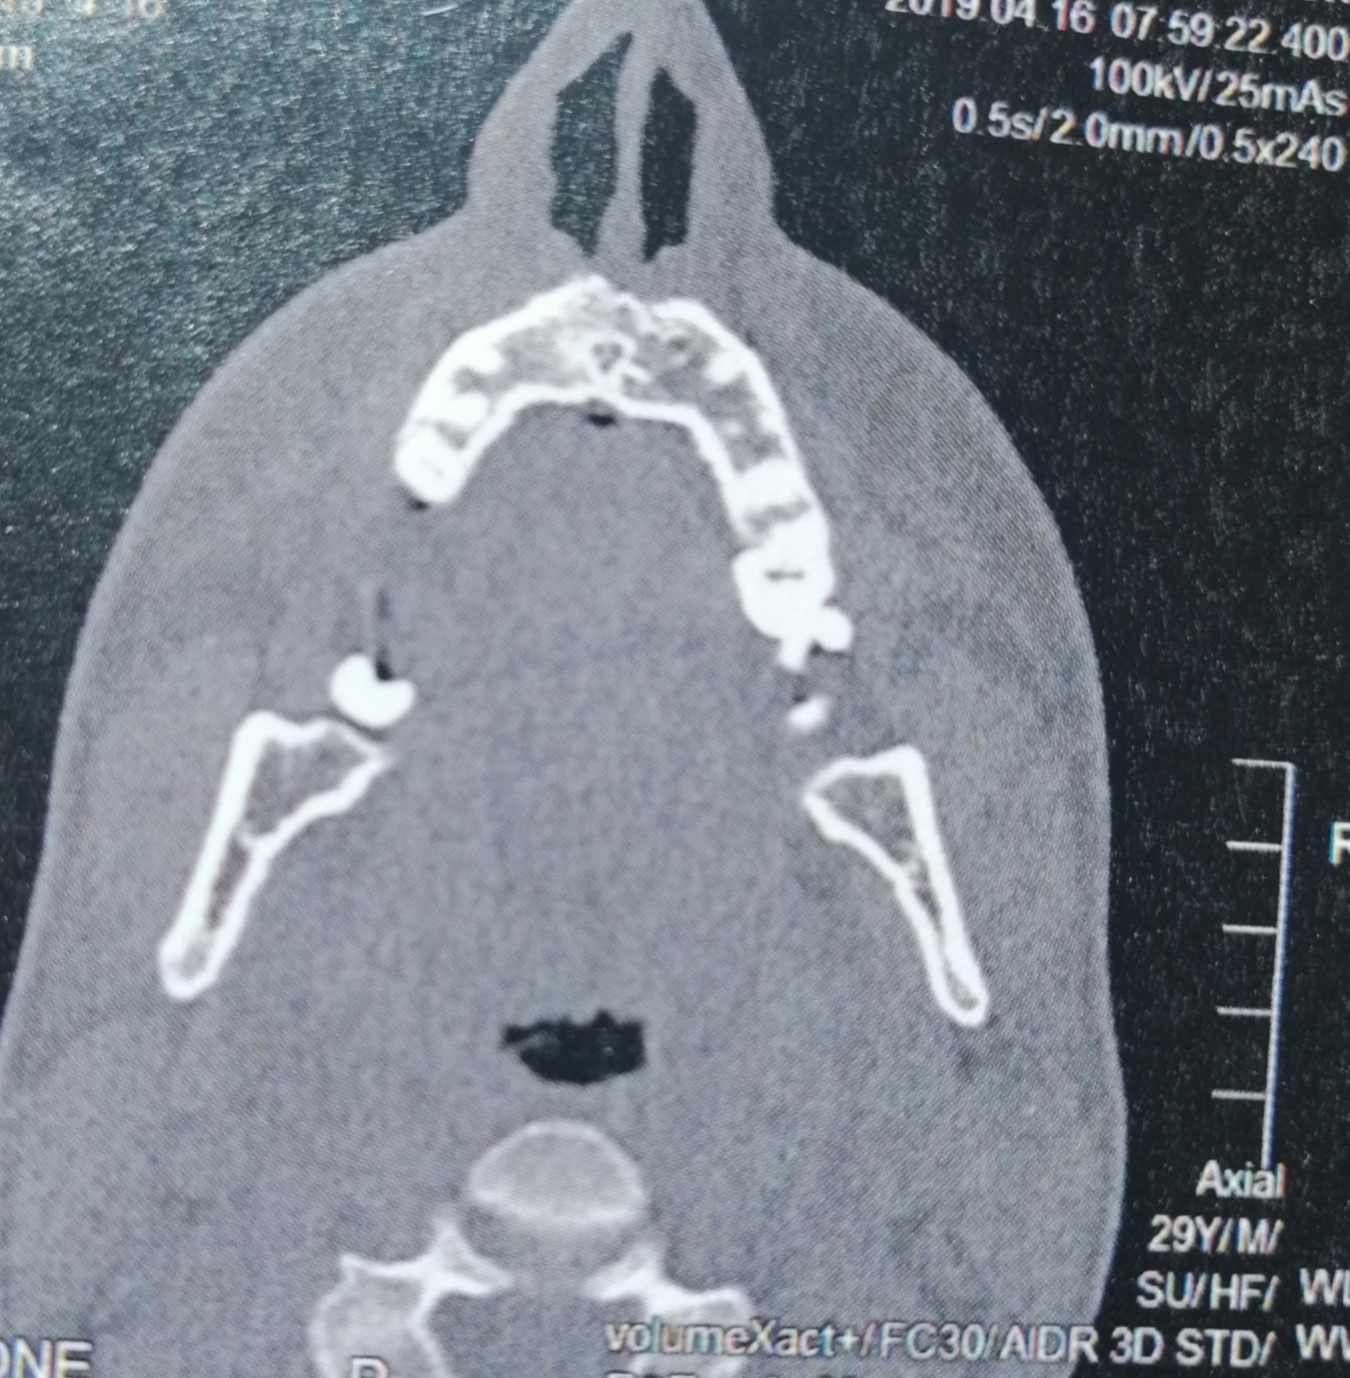

CT der Nasennebenhöhlen /Nase, alles ok? (kernspintomographie)

Source: www.gesundheitsfrage.net